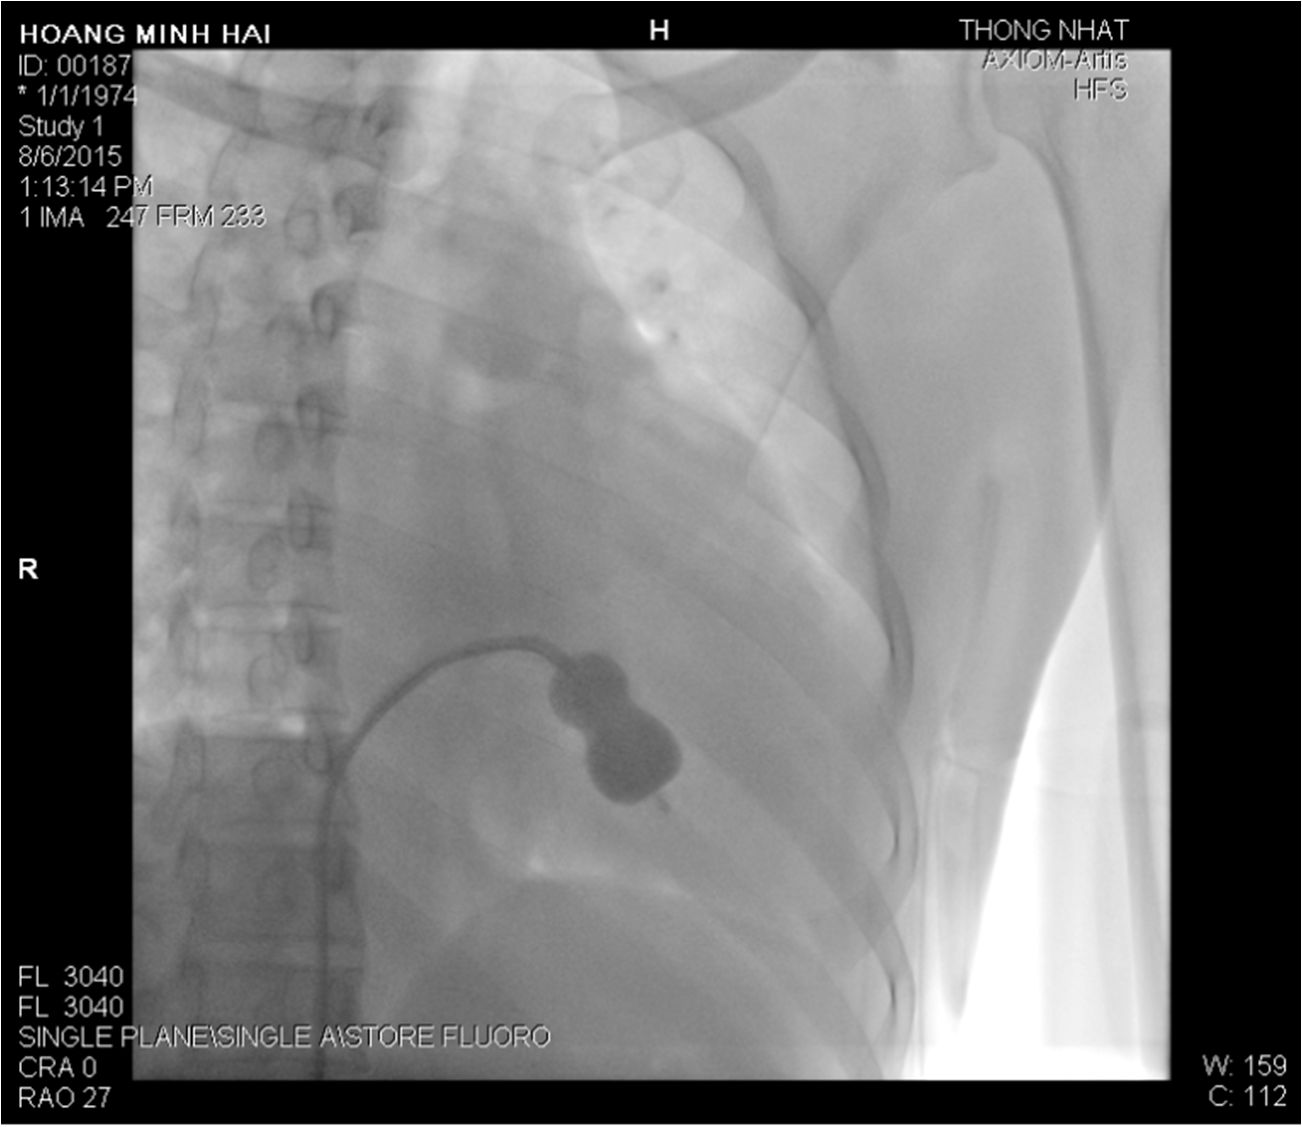

5.4 Can thiệp bệnh van tim qua da:

Nong hẹp nặng van 2 lá, van động phổi… giúp phòng ngừa/hạn chế phù phổi, suy tim

Một trường hợp nong hẹp van 2 lá khít hậu thấp bằng bóng Inoue